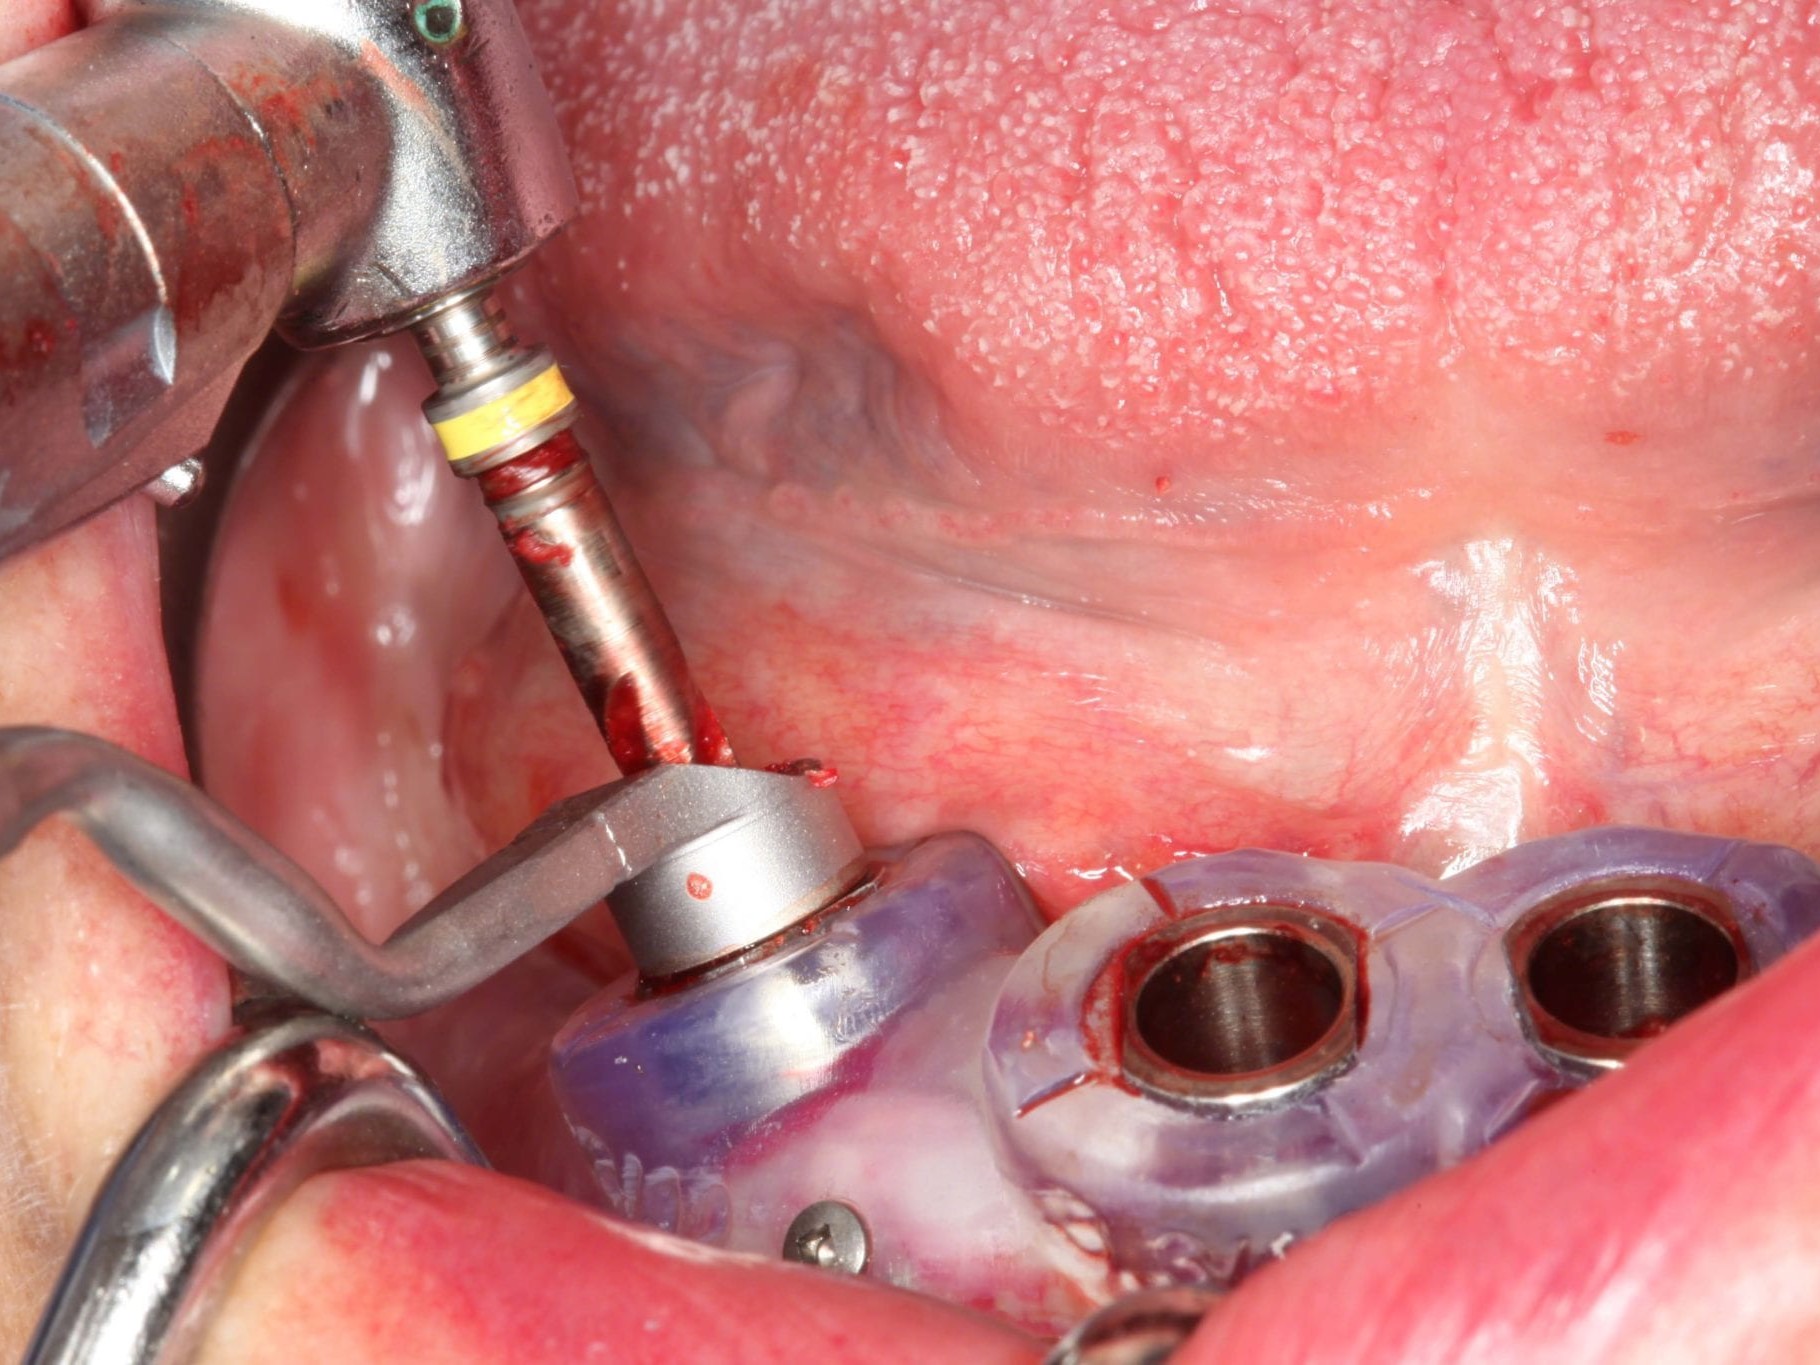

In Lokalanästhesie unter anästhesiologischem Standby mit intravenöser Antibiose mittels Clindamycin 600 mg 2mal/d wurde die Bohrschablone eingesetzt und mit Osteosyntheseschrauben fixiert (Abb. 8). Der Eingriff erfolgte nahezu flapless und somit transgingival. Nun erfolgte die Umsetzung des Straumann Hülse-in-Hülse-Konzeptes. Der Zylinder des Bohrlöffels wird in die an der Bohrschablone fixierten Hülse (Ø 5 mm) in den geplanten Regionen eingeführt. Für jeden Bohrerdurchmesser (Ø 2,2 mm und Ø 2,8 mm) ist ein entsprechender Bohrlöffel erhältlich. Jeder Bohrlöffel besitzt an seinen Enden Zylinder unterschiedlicher Höhe, die entsprechend chirurgischem Protokoll angewendet werden. Es wurden sämtliche Bohrstollen protokollgemäß aufbereitet (Abb. 9-11). Nach der Aufbereitung der Bohrstollen für die angulierten Implantate (Abb. 12-14) wurden die Straumann Bone Level Tapered Implantate (ø 3,3 mm) in regio 035 (Länge 10 mm) und 045 (Länge 12) gesetzt (Abb. 15). Abschließend wurden sämtliche Endpositionen der Implantate in regio 035 und 045 anhand der Lasermarkierungen am Übertragungsteil betreffend ihrer orovestibulären Ausrichtung exakt überprüft (Abb. 16). Nach Entfernung der Einbringhilfen und der Osteosyntheseschrauben konnte die Bohrschablone wieder entnommen werden. In regio 032 und 042 wurden nun die durchmesserreduzierten Straumann NNC (ø 3,3 mm Länge 12 mm) Implantate inseriert (Abb. 17, 18). Bei diesen Implantaten bedurfte es keiner Ausrichtung bezogen auf die orofasziale Ausrichtung. Hier musste die Insertionstiefe bezogen auf das NNC-Implantat beachtet werden (Abb. 19). Die NNC-Implantate wurden mit den entsprechenden Klebebasen versehen (Abb. 20). Danach wurden in regio 035 und 045 auf die Pro Arch Sekundärteile die dazugehörigen Retentionskappen (Abb. 21), die zur Vergrößerung der Oberfläche mit 120 μ Aluminiumoxyd abgestrahlt wurden, eingesetzt. Es erfolgte der typische Naht-Wund-Verschluss mit Einzelknopfnähten. Zum Abschluss erfolgte das prothetische Procedere mit der Eingliederung des Interimszahnersatzes in Okklusion (Abb. 22). Hierfür wurden die Retentionskappen und die Klebebasen mit dem Sofortprovisorium über ein selbsthärtendes fluoreszierendes kaltpolymerisierendes Paste-Paste-Kartuschensystem fixiert, dieser Zahnersatz extraoral versäubert (Abb. 23) und in der Mundhöhle refixiert (Abb. 24). Die Schraubenkanäle wurden mit Kunststoff verschlossen (Abb. 25). Abschließend erfolgte die radiologische Kontrolluntersuchung (Abb. 26).